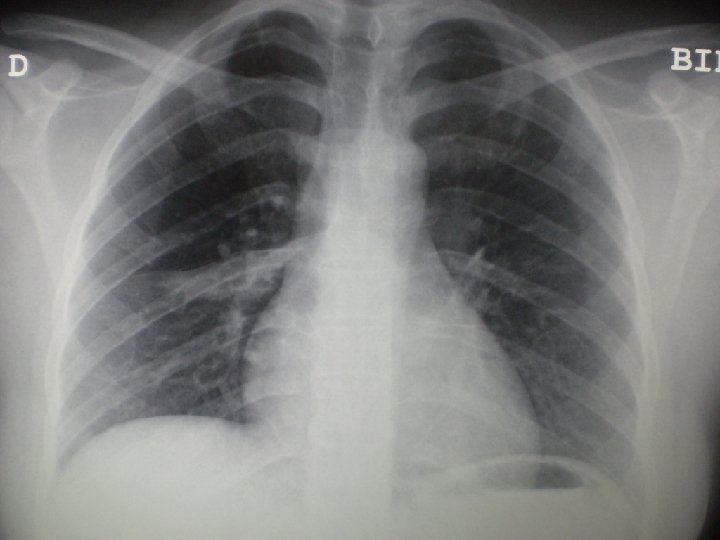

Paciente natural de Marruecos con adenopatías cervicales Exploraciones complementarias: Orina: sedimento normal. Parásitos en heces (x 3): negativos. Rx de abdomen: sin hallazgos patológicos. Rx de tórax: pequeño infiltrado en segmento postero-basal de LID, limitado por la cisura. Ecografía cervical: múltiples adenopatías laterocervicales derechas que se extienden por cadena yugular y espinal hasta hueco supraclavicular, algunas con centro necrótico.

Paciente natural de Marruecos con adenopatías cervicales Evolución: BAAR de esputo: NEGATIVOS TAC de tórax: lesiones nodulares en lóbulos superiores y pequeño infiltrado intersticio-alveolar en segmento 6 de LID. TAC cervical: Adenopatías cervicales derechas que captan contraste, con centro hipoatenuado en su interior en relación con necrosis, y cuyo tamaño oscila entre 1, 5 y 2, 5 cms.

Paciente natural de Marruecos con adenopatías cervicales Evolución - La paciente completó correctamente el tratamiento, presentando inicialmente fistulización de la adenopatía cervical sobre la que se realizó la PAAF, que tardó 3 meses en resolverse, quedando cicatriz retractil de la zona. -La Rx de tórax de normalizó, y no hubo problemas de tolerancia de tratamiento en los controles periódicos que se realizaron. -Se realizó estudio de convivientes (hermana), la cual realizó finalmente tratamiento quimioprofiláctico tras descartar infección tuberculosa activa.